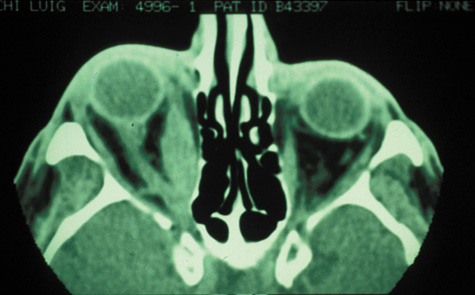

CT is particularly useful for imaging orbital and subperiosteal abscesses. Because the periorbit is not adherent to the orbital walls except at the suture lines, an abscess lifts the periorbit, creating a convexity in the orbital periosteum (Fig. 16). Usually subperiosteal abscess formation occurs adjacent to the involved sinus,25,64 but occasionally it occurs at a remote location such as the superolateral orbit.65 Gas may be found within a subperiosteal abscess or within the orbit, arising either from gas-forming bacilli or free communication with sinus air or from prior trauma (Fig. 17). 57,66 CT cannot accurately predict whether a subperiosteal mass represents exudate, inflammatory transudate, or hematoma.67,68

Fig. 16. Computed tomography showing subperiosteal abscess formation. Note elevation of orbital periosteum and convexity as pus elevates periorbit from the medial orbital wall.